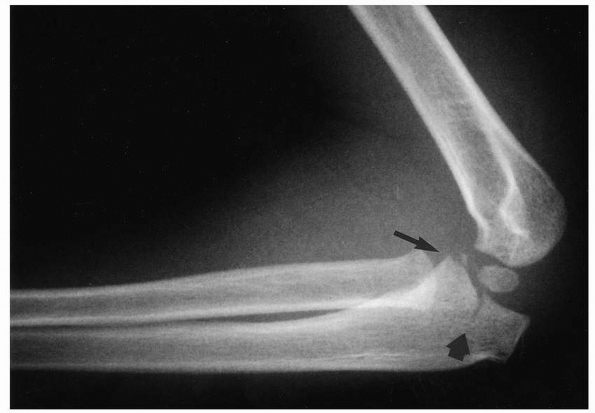

![]() |

FIGURE 16-14 Lateral radiograph of a 4–year-old child who sustained an elbow dislocation with a concomitant olecranon fracture (large arrow) and a coronoid fracture (small arrow).

FIGURE 16-15 A.

Anteroposterior and lateral radiograph of a 14-year-old male who sustained an elbow dislocation with an ipsilateral medial epicondyle fracture. B. Anteroposterior radiographs after a closed reduction. Note the entrapment of the medial epicondyle in the joint. C. This patient was treated with an open reduction to extract the medial epicondyle from the joint and an internal fixation using a cannulated screw that allowed rapid mobilization of his elbow. |